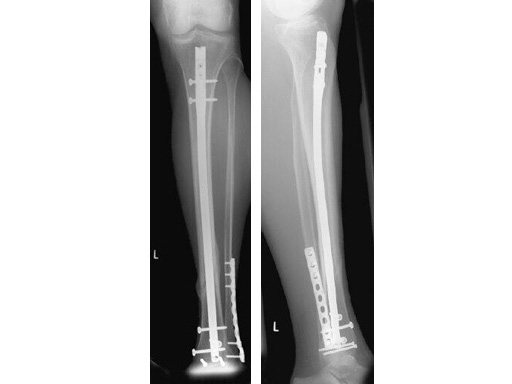

47-year-old man with closed 42-C3 fracture following a sports accident treated with ETNS.